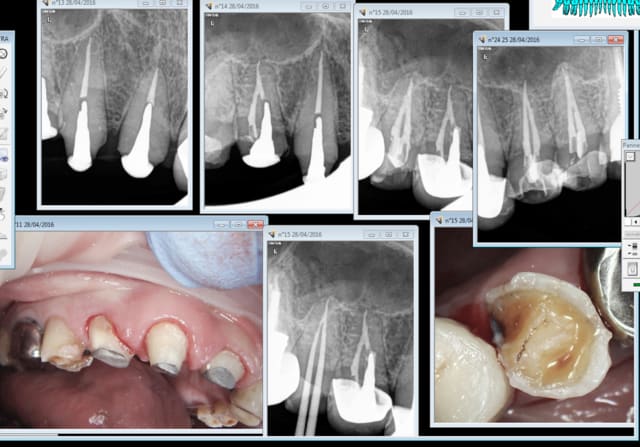

Ce que tu fais ? endo empreinte ic coiffe dans la séance.

1H 30 : pose ic coiffe 11 13 14 ( manque la 12 fait chier) endo taille empreinte 15 24 25.

Propre net sans bavures. -)

patiente CMU, tarif CMU rien à secouer. La rapidité te sauve.